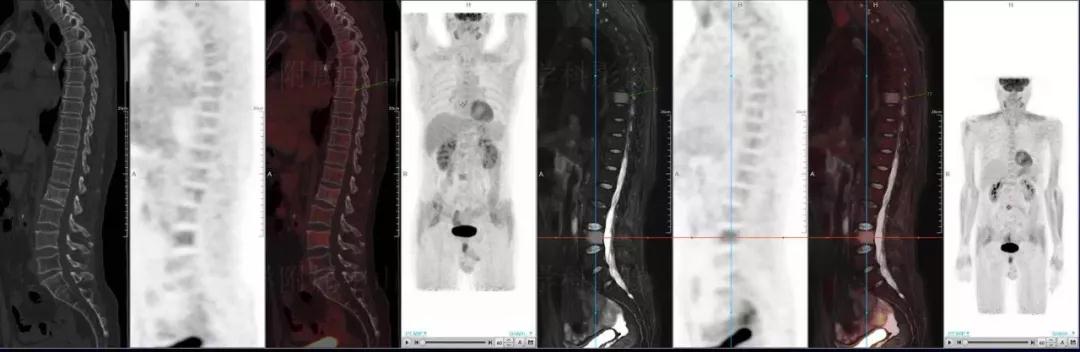

多發(fā)性骨髓瘤

中山醫(yī)院核醫(yī)學(xué)科基于聯(lián)影“時(shí)空一體”超清TOF PET/MR的融合顯像優(yōu)勢,進(jìn)行了大量的臨床掃描,發(fā)現(xiàn)多例由MGUS向多發(fā)性骨髓瘤轉(zhuǎn)變,并從中總結(jié)出了一定的共同征象,未來可能實(shí)現(xiàn)多發(fā)性骨髓瘤的早期篩查。此外,PET/MR在多發(fā)性骨髓瘤的療效評估方面,也存在顯著優(yōu)勢。

(男性,53歲。確診多發(fā)性骨髓瘤10月。經(jīng)過7周期VCD方案化療后,現(xiàn)行療效評價(jià)。)